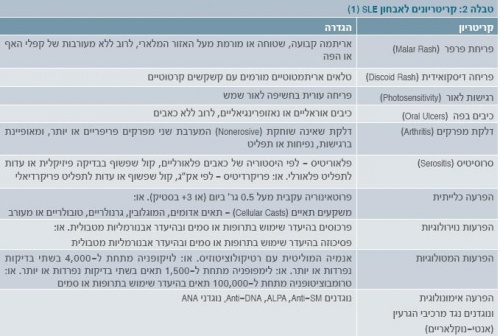

פרק הזמן הממוצע בין הופעת התסמינים לאבחנה הוא חודש אחד עד 3.3 שנים. התסמינים השכיחים בהתייצגות המחלה אינם כלייתיים. למטרת אבחנה, יש לזהות ארבעה תסמינים או יותר מתוך אחד עשר המקובלים בספרות (טבלה 2), המופיעים במקביל או בנפרד, במהלך תקופת המעקב. רוב מקרי המוות נובעים מזיהום, דלקת כליות (נפריטיס), אי ספיקה כלייתית, מחלה נוירולוגית או דימום ריאתי[1].